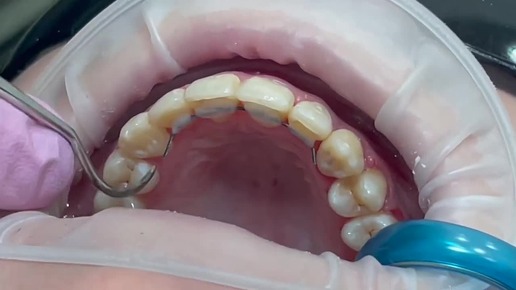

Установка ретейнера